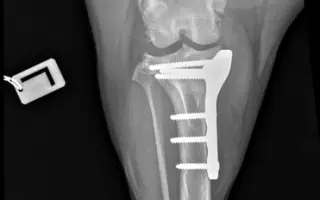

Veterinárna diagnostika odhalila dyspláziu bedrových kĺbov, chronické pretrhnutie väzov v oboch kolenách a pokročilú artrózu. Každý krok ju bolí, a hoci sa snaží byť veselá, vidno, že trpí.

Aby mohla opäť chodiť bez bolesti, potrebuje dve operácie kolien metódou TPLO. Prvá operácia je naplánovaná na ľavé koleno, druhá (po zahojení prvej) na pravé. Je to jej jediná šanca na návrat k normálnemu a dôstojnému životu.

Včera mala naša odvážna Lola prvú TPLO operáciu ľavého kolena.

Yesterday, our brave Lola had her first TPLO surgery on her left knee.